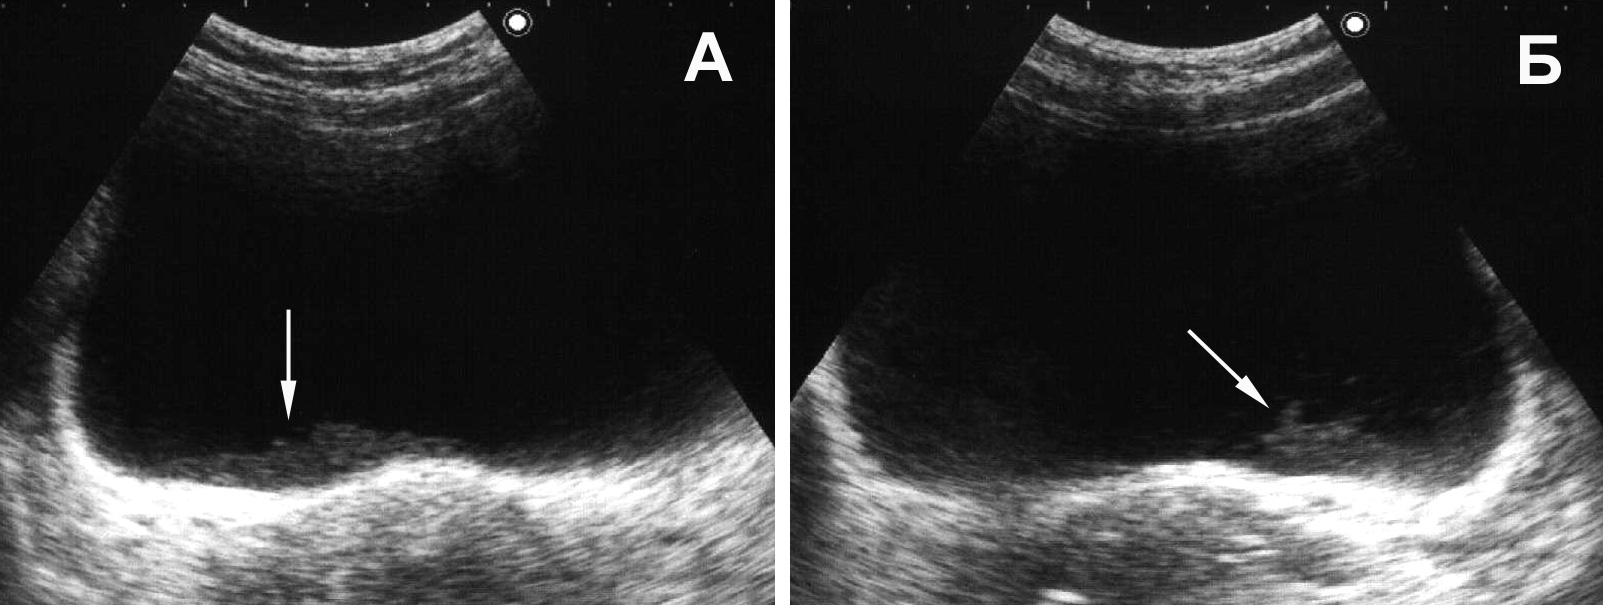

Рис. 16. Мочевой пузырь при цистите, лейкоцитурии. Определяется горизонтальный уровень нежной эхоструктуры (обозначен стрелкой), изменяющий свою форму и локализацию при перемене положения тела. (Поперечное сканирование, А − в положении пациента на спине, Б − на левом боку. Конвексный датчик 5 МГц, “Logiq-500”).